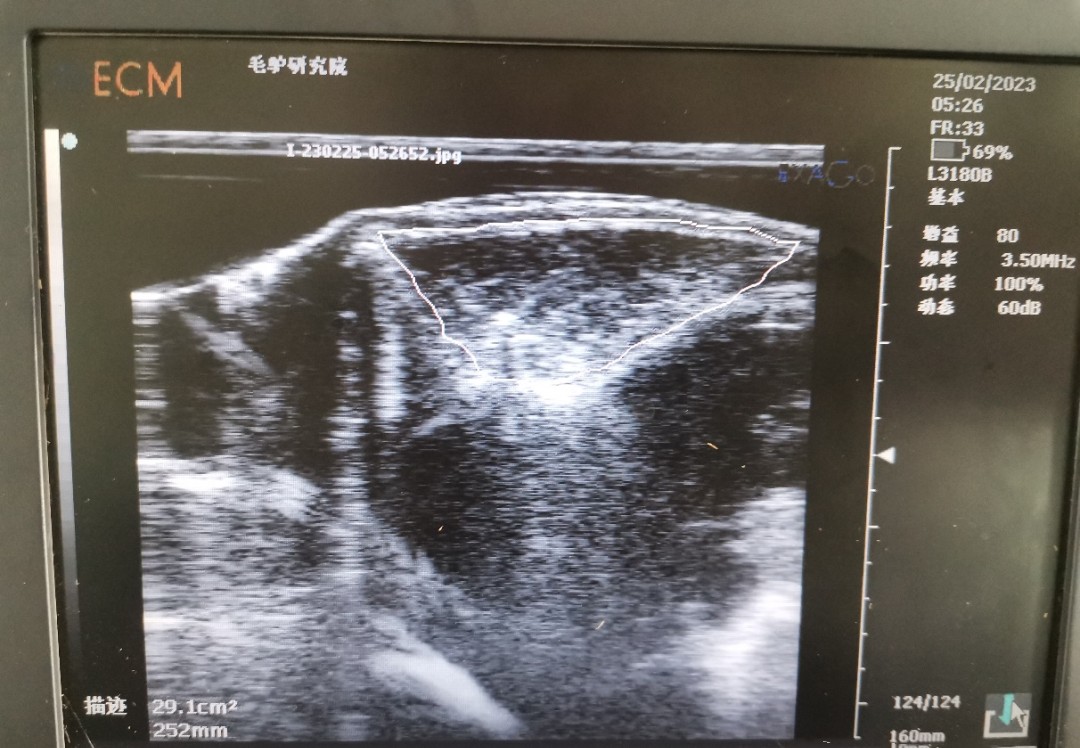

背膘活體測定可反應(yīng)家畜的膘情,而家畜的膘情與繁殖性狀相關(guān)。已有研究表明,豬的背膘和眼肌面積的研究已經(jīng)非常成熟,豬的背膘厚與繁殖性狀相關(guān),眼肌面積與生產(chǎn)性狀相關(guān)。同時,近年來在牛上也陸續(xù)開展背膘和眼肌面積工作的測定。背膘厚度及眼肌面積的活體測定,在指導(dǎo)動物的生產(chǎn)、精準飼喂、動物的遺傳改良中發(fā)揮較好作用,使家畜育種和生產(chǎn)工作取得了較大進展。但此技術(shù)在驢上應(yīng)用卻較少。

為了彌補背膘和眼肌面積在驢上的應(yīng)用空白,我團隊開展了德州驢背膘和眼肌面積的測定工作。為更好的驗證所測定的結(jié)果,團隊成員在已屠宰的德州驢上進行確認,確保測量結(jié)果準確性。背膘厚及眼肌面積性狀在驢遺傳育種上的應(yīng)用將為選育更加優(yōu)良的德州驢種質(zhì)提供了新的指標,可加快驢種質(zhì)創(chuàng)新步伐。